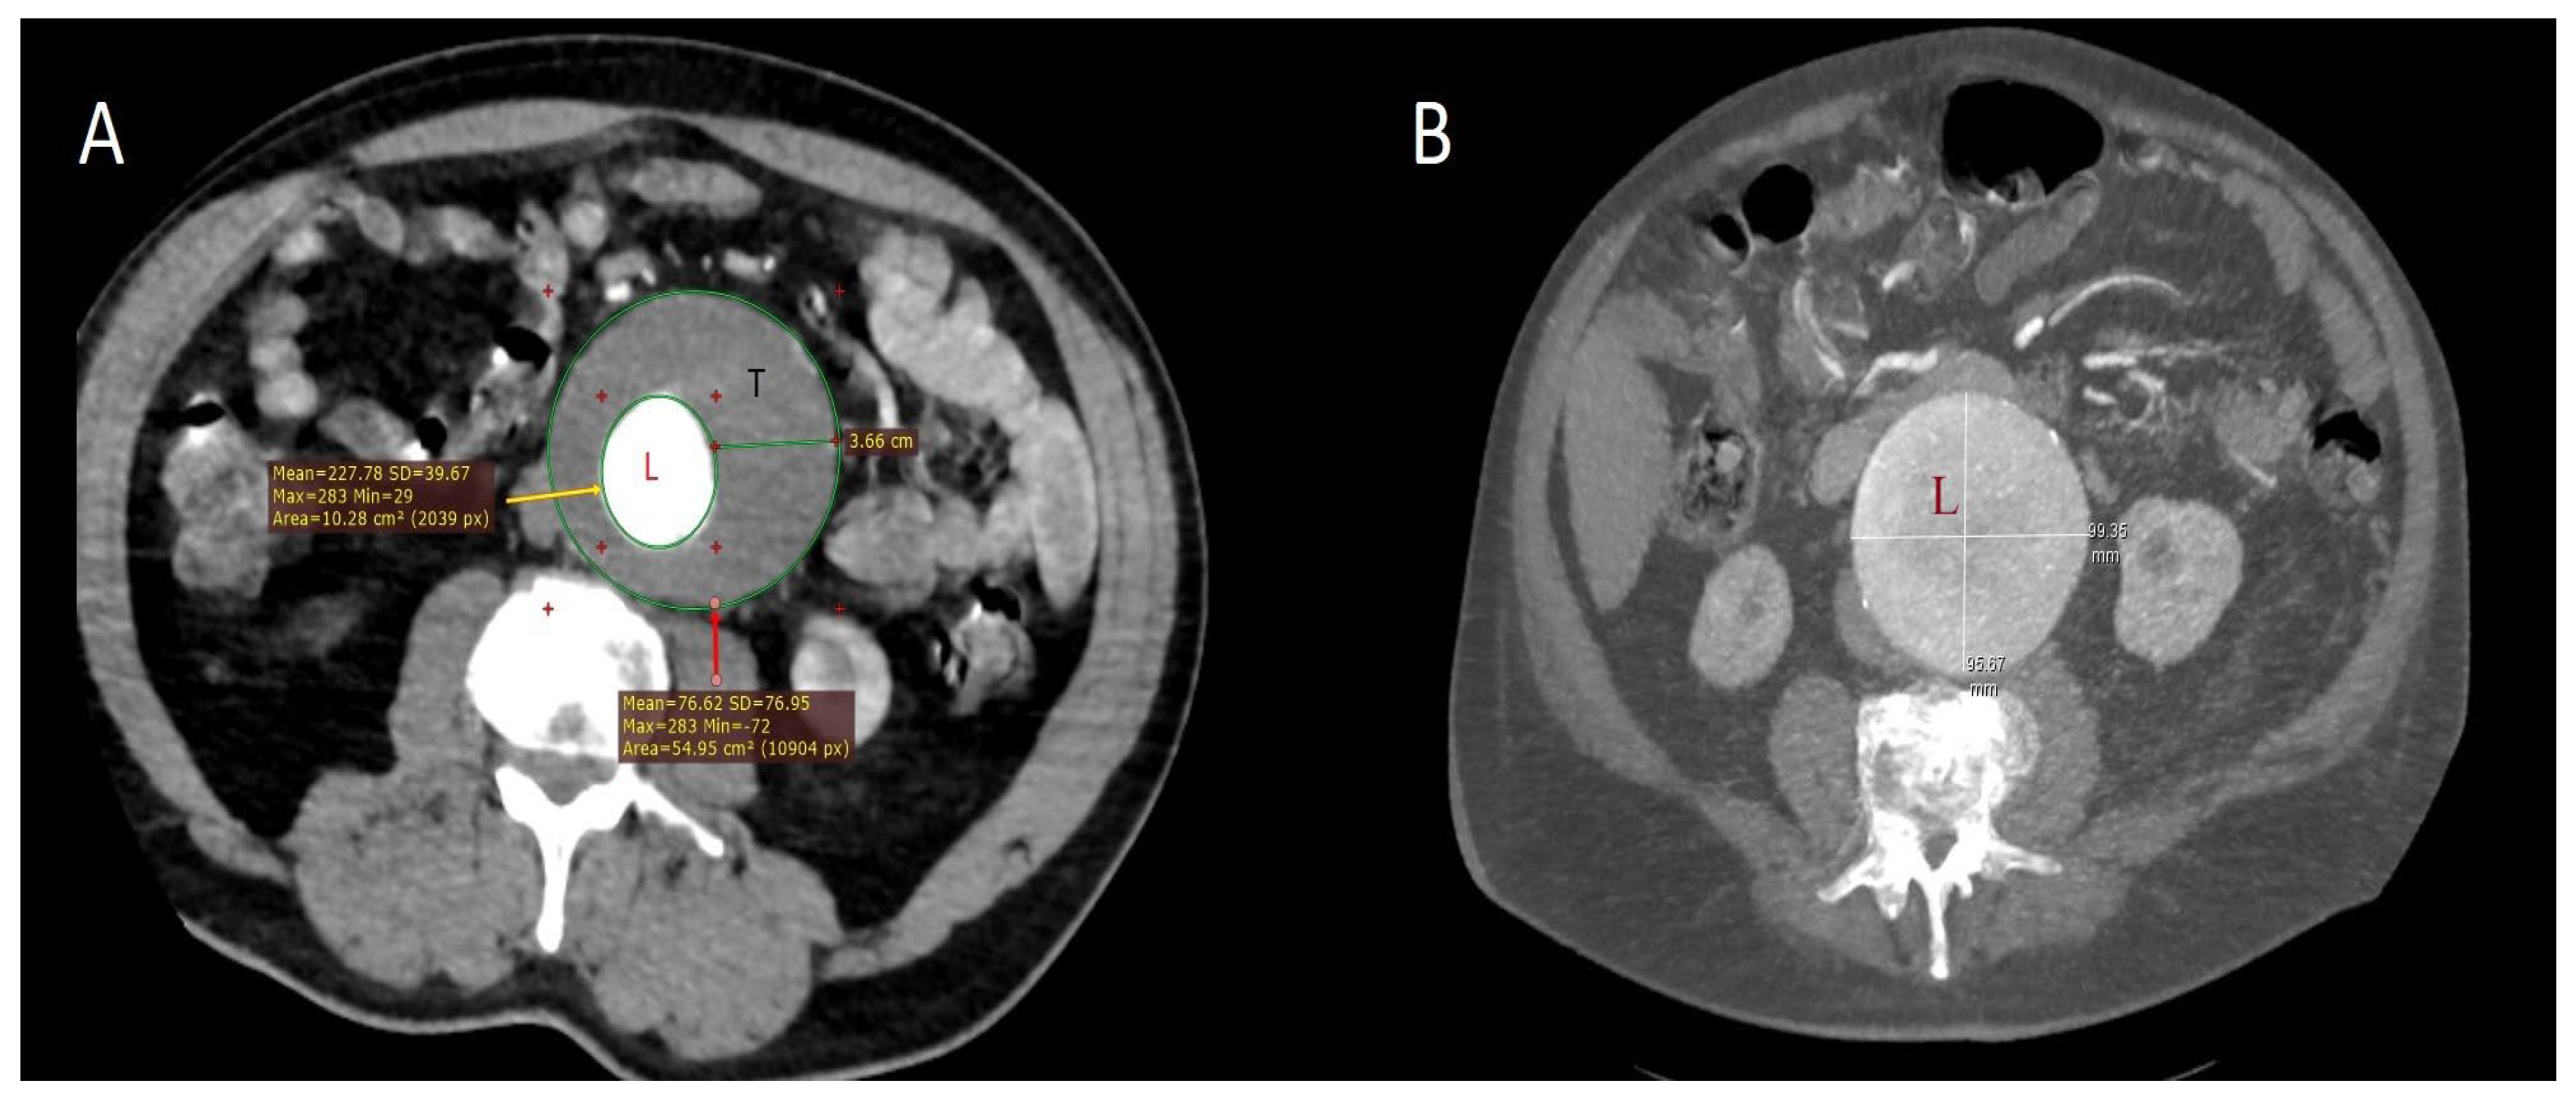

| Aneurysm diameter (transverse), mm, median (Q1–Q3) | 77 (65–83) | 65 (61–70) | <0.001 |

| Intramural thrombus thickness, mm, median (Q1–Q3) | 25 (21–28) | 20 (16–25) | <0.001 |

- Kakisis, J.D.; Moulakakis, K.G.; Antonopoulos, C.N.; Mylonas, S.N.; Giannakopoulos, T.G.; Sfyroeras, G.S.; Karakitsos, P.; Liapis, C.D. Volume of New-Onset Thrombus Is Associated with the Development of Postimplantation Syndrome after Endovascular Aneurysm Repair. J. Vasc. Surg. 2014, 60, 1140–1145. [Google Scholar] [CrossRef]